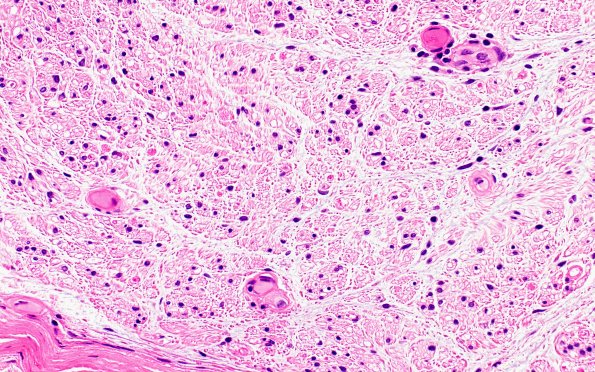

Hypoxia-Ischemia, fetal-neonatal

5A3 (Case 5) H&E 40X 3